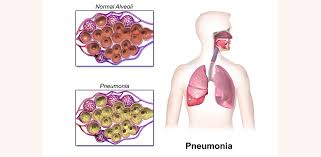

Lung Infection Specialist Clinic in Thazhambur

A pulmonologist is the specialist doctor who diagnoses and treats conditions and diseases of the respiratory system, including the lungs. They are also commonly referred to as lung doctors, chest doctors, or lung specialists. If you are experiencing a lung infection, a pulmonologist would be the right specialist to see. Arca Clinic DR.VISWWAMBHAR one of the best Lung Infection Specialist near by Thazhambur.